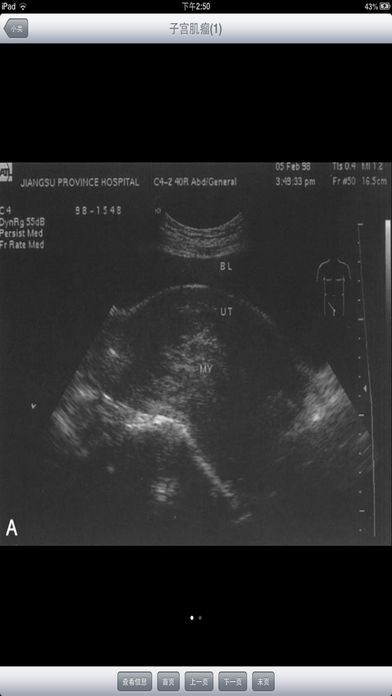

随着医疗卫生事业的发展,各种医疗仪器层出不穷的涌现,给临床诊断工作带来了极大的帮助,尤其是B超、CT、X光等影像学检查的应用,大大的提高了临床诊断的正确符合率和准确性。 基层诊断医生对影像知识缺乏了解,不能结合临床有重点的剖析,正确地加以辨别,诊断难以深刻,而且易忽略不典型病变,产生误诊、漏诊;另外,基层医生缺乏必要的影像读片知识,从而影像了诊断水平的提高。 影像诊断系统能够指导各级医生如何识别B超、CT、X光等临床表现,分析各种疾病的影像特征,做出更符合临床的影像诊断。每一张影像都配有表现和评述,是医生和医学院校的学生学习影像诊断入门的必备软件。